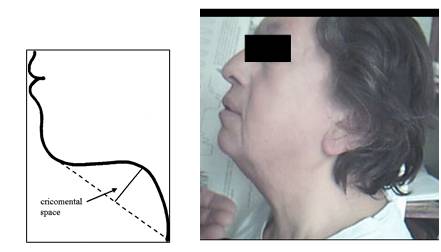

Los signos frecuentes se presentan en la Tabla 6. La figura 3, La figura 4, La figura 5 y La figura 6 describen los hallazgos de importancia en el examen de cuello y de la orofaringe, que habitualmente son escasamente destacados en la enseñanza de la semiología. La circunferencia de cuello fue de 45,9 ± 3,9cm en hombres (normal hasta 42) y 41,8 ± 3,7cm en mujeres (normal hasta 38). El espacio crico-mental se evaluó cualitativamente15. En el examen de la orofaringe, se evaluaron los grados de Mallampati16, como predictores de severidad de apneas del sueño. Los grados más altos se asociaron a IAH mayores, aunque en forma no significativa (Figura 7).

Figura 4: En el panel de la izquierda (tomado de Tsai WH 26): esquema de la distancia crico-mental normal. A la derecha: foto de paciente con distancia crico-mental nula.